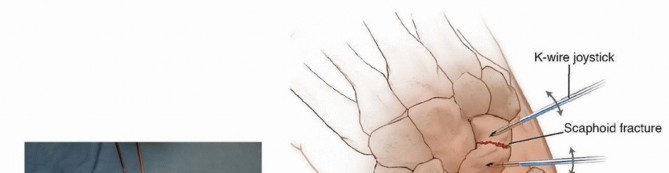

Insert an Acutrak 2, mini-Acutrak 2 screw (Acumed, Beaverton, OR), or other cannulated headless compression screw of appropriate length (at least 4 mm shorter than the measured scaphoid length) to within 1 to 2 mm of the distal surface. The tip of the screw should not penetrate the distal surface, and the proximal end of the screw should rest 2 mm deep to the proximal articular cartilage ( TECH FIG 2D,E). Confirm satisfactory screw position and fracture reduction with fluoroscopy. The screw should be inserted down the central axis of the scaphoid. If any doubt exists, use the arthroscopic portals to confirm that the screw is buried in the scaphoid. The 3-4 portal and the radial midcarpal portals provide the best view to ensure that the fracture is adequately reduced and that there is no violation of the midcarpal joint. ### Displaced Scaphoid Waist Fracture Insert two percutaneous 0.062-inch smooth Kirschner wires dorsally into each fragment perpendicular to the long axis of the scaphoid to be used as joysticks to reduce the fracture ( TECH FIG 3A,B). Position the wrist as previously described. The guidewire from the Acutrak 2 system (or the surgeon's chosen system) is inserted from proximal to distal, starting dorsally and aiming for the central axis of the distal fragment. The guidewire is driven through the distal fragment and out through the volar skin of the hand. The protruding tip is then pulled volarly until the wire is only in the distal fragment ( TECH FIG 3C).24, 25 115

### TECH FIG 2 • A-C. Before screw insertion, the position of the Kirschner wire must be changed from its position used for arthroscopy. The Kirschner wire should be driven from volar to dorsal until the distal end lies just beneath the articular surface of the scaphoid. D,E. Screw fixation of minimally displaced scaphoid fracture via the dorsal percutaneous technique. The screw tip should rest within 1 to 2 mm of the distal cortex. Excellent compression should be obtained with this technique. The proximal fragment, which is now freely mobile, is reduced manually using the Kirschner wire joysticks. Once the fracture is reduced, the central guidewire is driven from volar to dorsal into the proximal fragment, securing it in place ( TECH FIG 3D).24, 25 The guidewire is further advanced from volar to dorsal until its distal tip is just within the subchondral bone of the distal articular surface. This allows for measurement of the screw length as previously described.

### TECH FIG 3 • A. Reduction of a displaced scaphoid waist fracture using Kirschner wire joysticks. B. The Kirschner wire joystick technique for fracture reduction.

An additional 0.045-inch Kirschner wire is inserted parallel to the guidewire to prevent rotation of the scaphoid fragments during reaming and screw implantation. Maintenance of reduction during and after screw insertion is confirmed with fluoroscopy, and all wires are subsequently removed. 116

C. The guidewire is pulled volarly until it remains only in the distal fragment. The joysticks are then utilized to reduce the fracture. D. The guidewire is driven from volar to dorsal, transfixing the proximal fragment.